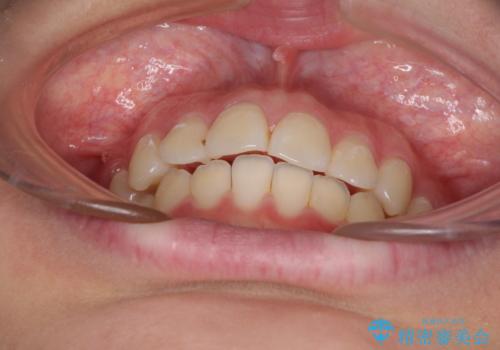

前歯のデコボコを改善 インビザライン矯正

- 口元のデコボコを気にして来院された患者様です。

前歯の捻れにより口元が閉じにくくなっていたため、歯列全体の側方への拡大と、歯と歯の間を少し削ってスペースを獲得することとしました。

ゴムかけをしっかりと行ってもらい、スッキリとした口元に仕上げることができました。